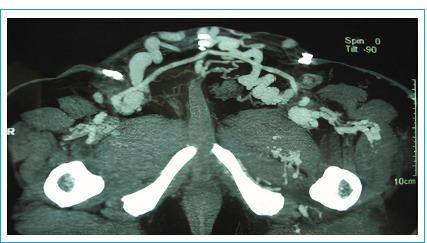

Congenital morphological disorders of the vascular bed, especially located on the main arteries and veins of the extremities, can cause chronic venous insufficiency and venous claudication, creating exacerbated symptoms for the patient and which require intervention. In cases where interventional radiology is insufficient, surgical approaches should be prioritized. Sixty-five years old male patient admitted to our clinic with increased bilateral lower extremity swelling which revealed to be chronic venous insufficiency secondary to congenital disorders. Sapheno-femoral veno-venous bypass (Palma operation) was performed, and patient was discharged on post-operative day 15 without further complaints. Palma Operation is an effective surgical treatment option in venous malformations of lower extremity where interventional radiology is not sufficient.

血管床的先天性形态学疾病,尤其是位于四肢主要动静脉的疾病,可导致慢性静脉功能不全和静脉性跛行,给患者带来加剧的症状,需要进行干预。在介入放射学方法不足的情况下,应优先考虑手术方法。一名65岁男性患者因双侧下肢肿胀加重入住我院,检查发现是先天性疾病继发的慢性静脉功能不全。进行了大隐静脉-股静脉静脉旁路手术(帕尔马手术),患者术后第15天出院,无进一步不适主诉。帕尔马手术是介入放射学方法不足时治疗下肢静脉畸形的一种有效手术选择。